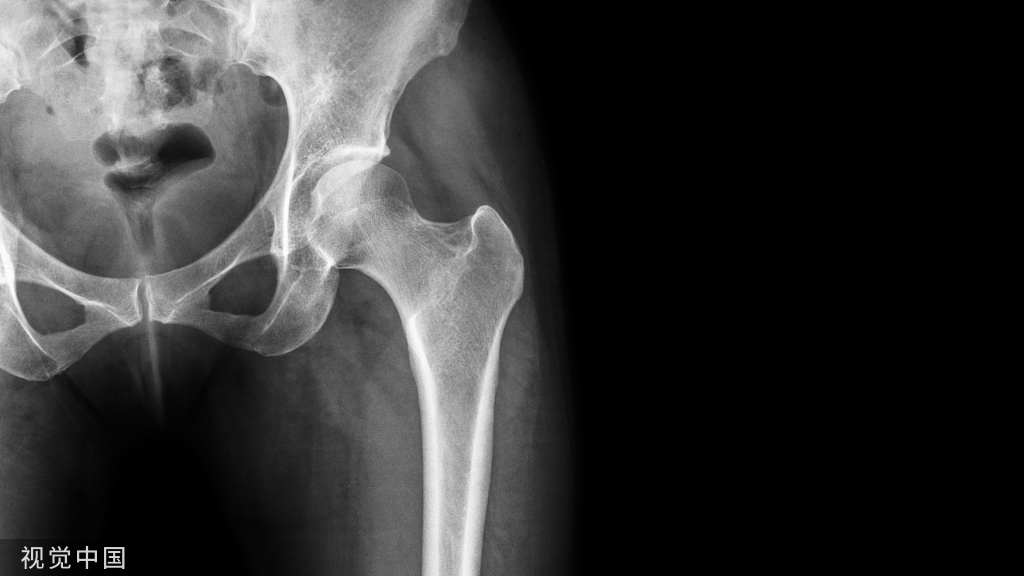

17.Pipkin骨折

股骨头骨折伴髋关节后脱位。常见于屈膝屈髋位汽车仪表盘损伤。